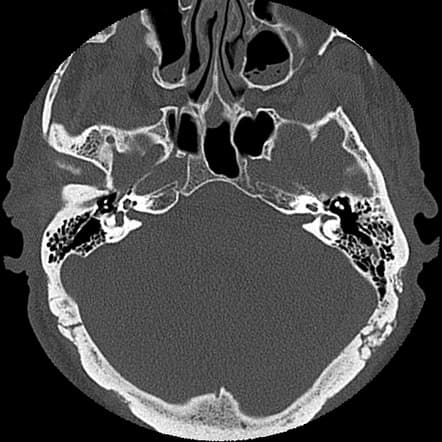

Detailed examination of the middle ear and surrounding bone structures with Temporal Bone CT Scan. Reliable medical imaging center solutions for early diagnosis.